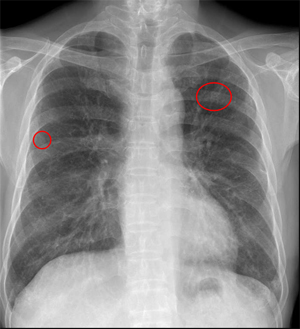

両肺に数少ないが多発結節(小葉との関係は判断困難)の出現、出現速度は速く、増大経過(LVFX抵抗性)

2010.05.27 抗生剤( LVFX )投与開始後 解熱なし

2010.06.2) 初診から5週後

増大したものの一部に空洞形成、左上区の最大のものの空洞内には同心円状・索状構造がみられる